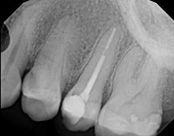

This patient presented with pain when chewing. Diagnostic testing was done and determined it was the lower molar. The diagnosis was: pulpal necrosis, symptomatic periradicular periodontitis. Root canal treatment was performed with laser disinfection. The tooth had a crown and we accessed the tooth through the crown. We saved the tooth and the crown.